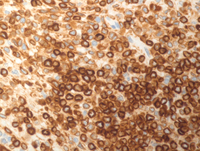

CD20 and CD79a IHC

As a result of anti--CD20 therapy, CD20 immunostain (first image) is negative. However CD79a immunostain is strongly positive in all receptors at low power as well as that high-power confirming B-cell lineage.